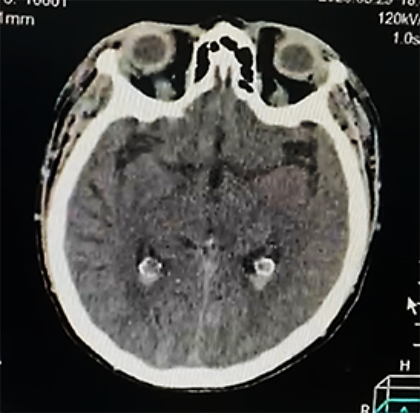

Ingresa con los diagnósticos de: accidente cerebrovascular hemorrágico (peri-troncal); Crisis hipertensiva tipo emergencia; hiponatremia hipotónica hipervolemica; enfermedad renal crónica KDIGO 5 en hemodiálisis; diabetes mellitus tipo 2 mal controlada e hipertensión arterial sistémica. Permaneció bajo monitorización continua de la presión arterial, asociado a vasodilatadores endovenosos (nitroprusiato de sodio 3-5 ug/k/min), seguimiento por el servicio de nefrodialisis, para continuar terapia de reemplazo renal; por otro lado fue evaluado por el servicio de neurocirugía quien indico por el momento tratamiento médico, asociado a medidas de protección cerebral; además fue evaluado por el servicio de cardiología, solicitando una ecocardiograma transtorácico: Hipertrofia concéntrica del ventrículo izquierdo, motilidad regional preservada, fracción de eyección de ventrículo izquierdo (FEVI) 66%; se realizó una Rx de tórax PA que mostro leve redistribución vascular pulmonar, catéter venoso central in situ; por otro lado en fecha 24/05/23 se realiza una angio resonancia magnética de cerebro que muestra hemorragia subaracnoidea y sangre en area prepontina, premedular y peripeduncular, además de cisuras frontoparietooccipitales, dilatación de tercer ventrículo, enfermedad vascular tipo microangiopatia (Figura 2a, b).